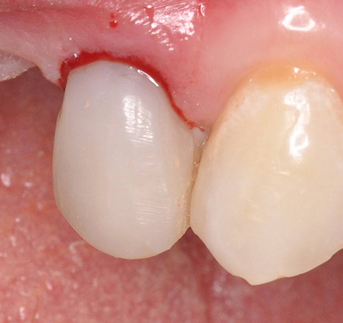

После завершения эндодонтического лечения и стабилизации состояния зуба врач-ортопед провёл подготовку зуба под протезирование. Изготовлена и зафиксирована коронка. (Фото 2 и 3).

Результат: Болевые ощущения при накусывании полностью устранены, дискомфорт при жевании отсутствует. Зуб сохранён и полноценно восстановлен. После установки керамической коронки восстановлены анатомическая форма и жевательная функция.